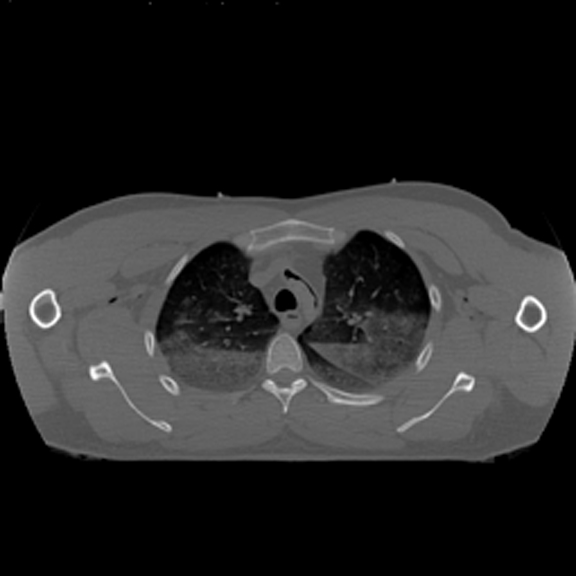

Horizontal CT Section at this level